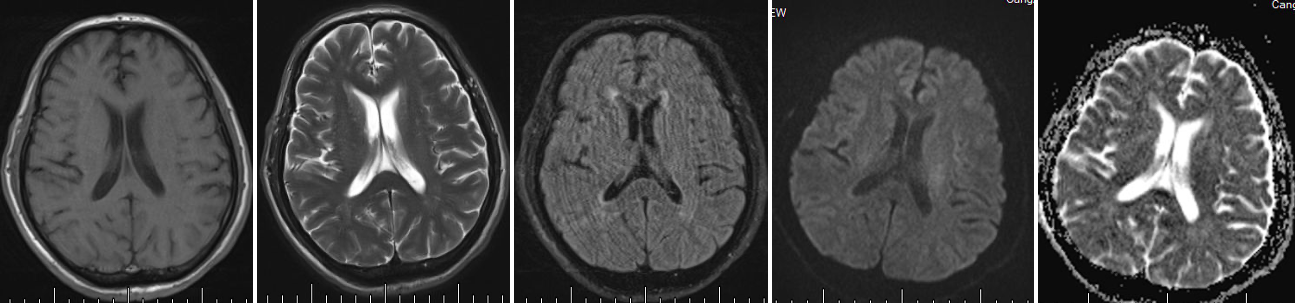

二、神经影像

头MR(2024-10-20)左侧放射冠区可见小片状DWI高信号影,ADC信号减低。双侧侧脑室旁可见斑片状T2W及T2Flair稍高信号影,边界模糊。双侧放射冠区、额叶及底结区、脑干、双侧小脑半球多发小片状T2W及T2Fliar高信号影,T1W呈稍低信号。 【影像诊断】 :左侧放射冠区急性脑梗死;双侧脑白质脱髓鞘改变;颅内多发腔隙性脑梗死、缺血灶;双侧筛窦炎、上颌窦炎。

头DWI+MRI(2024-11-25):头DWI可见右侧底结区点状高信号影,ADC歼敌。双侧大脑半球白质区见斑片状高信号影。【影像诊断】:右侧基底节区急性脑梗塞;颅内多发缺血灶、脑梗塞;双侧大脑半球异常信号影,请结合临床。双侧乳突炎。三、临床印象